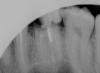

posman Опубликовано 7 ноября, 2010 Поделиться Опубликовано 7 ноября, 2010 Уважаемые специалисты, интересует ваше мнение:1.Верхняя 6-ка слева - депульпированный зуб был восстановлен на штифте, со временем половина откололась.2. Верхняя 7-ка справа - депульпированный зуб, пломба выпала, остался практически один корень. Можно ли восстановить зубы вкладками, или необходимо удалять с последующей установкой имплантов? Снимки прилагаю.Заранее благодарю за ответ! Ссылка на комментарий

posman Опубликовано 7 ноября, 2010 Автор Поделиться Опубликовано 7 ноября, 2010 т.е. каналы необходимо перелечивать (они уже пломбированы)? прошу консультации, т.к. один протезист от восстановления 6-ки отказался, пояснил, мол кариес затронул корень и гарантий на то что он(корень) не развалится - нет... по снимкам можно дать какой-то прогноз? сорри, малость ошибся, последний пост(вопрос) про семёрку (:-), да, и про 6-ку подскажите плз.? Половина пломбы отвалилась вместе со штифтом, часть осталась в корне. Ссылка на комментарий

Bier Опубликовано 8 ноября, 2010 Поделиться Опубликовано 8 ноября, 2010 по второму снимку точно удалять, первый - во рту смотреть надо Ссылка на комментарий